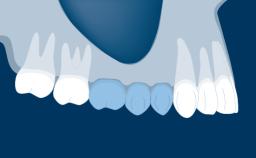

Fixed and removable prosthodontic implant therapy for restoration of the edentulous maxilla is both complex and challenging. Careful assessment and planning is needed in each individual case to explore whether a fixed or a removable solution will be the more suitable to satisfy the patient’s preference for optimal esthetics, phonetics, comfort and function. This Learning Pathway explores the prosthodontically driven treatment planning based on structured assessment, considered diagnosis and practical application in clinical case examples.

Edentulous Maxilla Fixed vs. Removable Prosthodontics Planning Principles Prosthodontic Planning & Procedures Prosthodontic Planning & Procedures